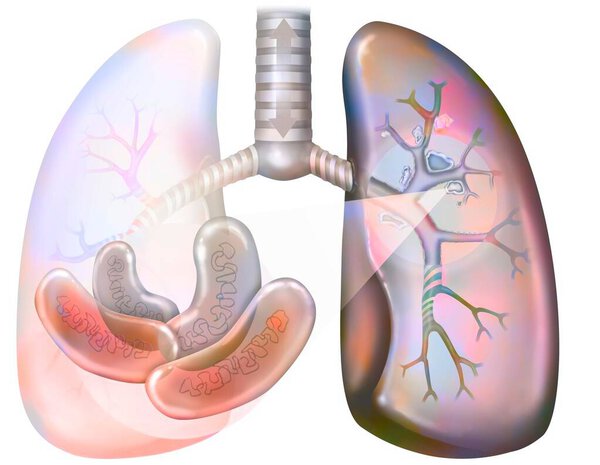

- Рак легких курильщика (с наличием депозитов смолы в бронхах).

Рак легких курильщика (с наличием депозитов смолы в бронхах).

Рак легких курильщика (с наличием депозитов смолы в бронхах).